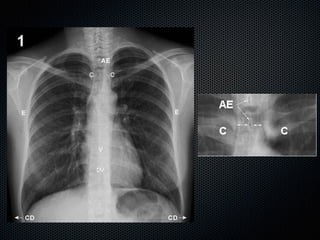

Características de una Radiografía de

Tórax de Calidad

Esqueleto Regional Toráccico de D3 se

proyecta en el punto medio entre las

articulaciones esternoclaviculares.

Los bordes internos de las escapulas se

proyectan por fuera de la caja costal o

toca las partes laterales de las costillas.

El tórax se visualiza totalmente si puede

observarse la laringe y ambos senos costo

frénicos